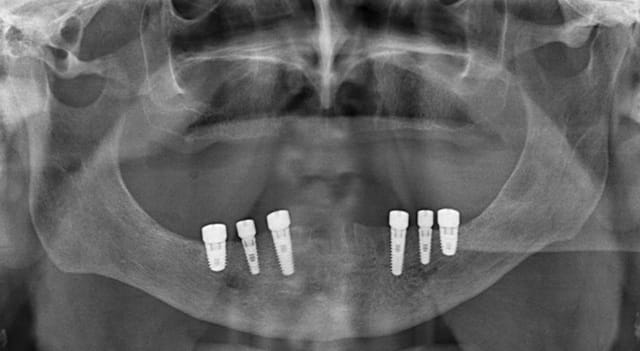

8 implants à la mandibule, c'est ceinture plus bretelles.

à 3 mois aucun probleme.

bien sur il n'y a pas d'extension ou de bras de levier demesuré, les insicives ne sont quasiment pas fonctionnelles, ce qui ne sera pas le cas pour la prothese d' usage.